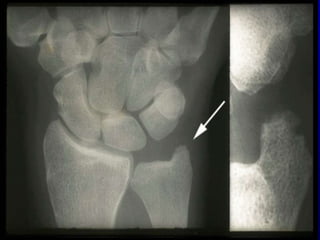

IMAGING

Radiografia: gold standard per la valutazione del danno erosivo;

particolarmente utile per il followup della malattia, per definirne la severità in

un determinato momento e determinare l’efficacia della terapia (follow-up

annuale o addirittura semestrale).

>metodo di Larsen e metodo di Sharp

Erosioni articolari

• L’ Rx convenzionale rappresenta il mezzo più diffuso, rapido

ed economico per evidenziare le erosioni articolari; in realtà

tale tecnica non ne consente, in molti casi, una

individuazione precoce

• Viene quindi ribadita l’importanza dello strumento ecografico

e in particolare dell’eco power-doppler, in quanto mezzo

certamente più economico della RM e più efficace dell’ Rx

convenzionale per evidenziare precocemente le erosioni e la

attività infiammatoria del panno sinoviale

• tutte le metodiche diagnostiche sono comunque utili, ma

l’ecografia è più sensibile

• La presenza di erosioni (a prescindere dalla tecnica

impiegata per la diagnosi) è un importante indice di

aggressività